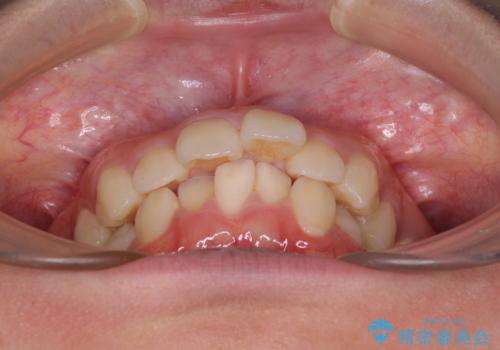

- 前に傾斜して飛び出した上顎前歯を気にして来院された患者様です。

上下前歯の前後差が大きく、下顎前歯が隠れるほど深い咬合で、咬合力が強い状態でした。

口元の突出感を改善するために、上下左右の第一小臼歯4本を抜歯し、ワイヤー装置にて矯正治療を行うこととしました。